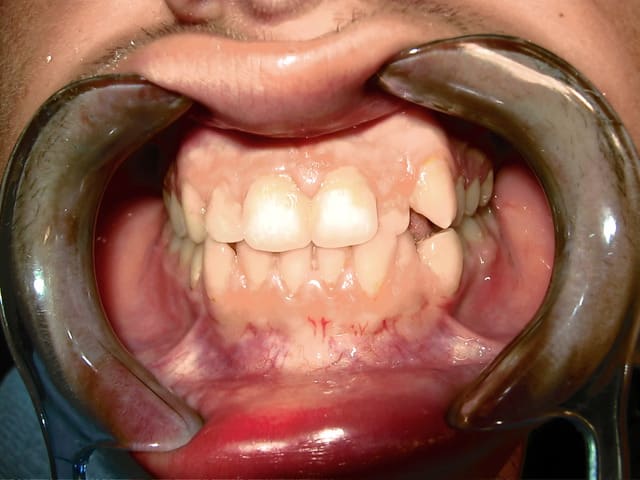

bonjour je vous presente mon cas :

j'ai recu un patient agé de 19ans , qui veut aligner ses dents.

Aprés l'etude du cas le diagnostic est le suivant :

CL1 squelettique tendance Cl3

hyperdivergent

Proalveolie sup

Normoalveolie inf avec une tendance a la retroalveolie

Prochélie

Cl3 dentaire molaire droite et gauche et Cl1 dentaire canine droite et gauche

Le plan de traitement est le suivant :

Pour resoudre le probleme d'encombrement en bas , extraction de la 34 et 44

et en haut on a une Cl3 dentaire , je penses qu'il faudrait extraire la 15 et 25 pour permettre l’avancé des molaires ?

Sinon on extrait que la 14 et 24 et les élastiques permettront cette avancé ?

et pourquoi pas tenter de tout réaligner sans extraire?

Je suis tout à fait d'accord avec pluton. Commencer à niveller en ayant un ancrage postérieur et finir avec des EL II. Ton cas est tout à fait réalisable sans extractions. Si tu pratiques du Damon (et ça va déchaîner les passions)c'est un cas classique.